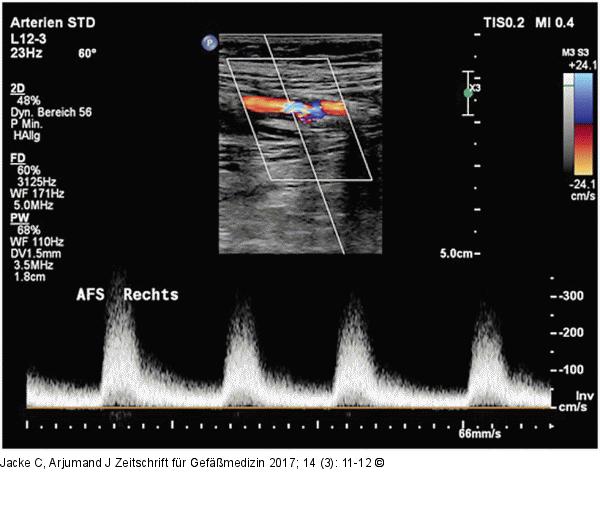

Abbildung 1: AFS-Stenose Duplexsonographischer Beweis der AFS-Stenose innerhalb eines Stents zu Beginn der Untersuchung. |

Duplexsonographischer Beweis der AFS-Stenose innerhalb eines Stents zu Beginn der Untersuchung. |